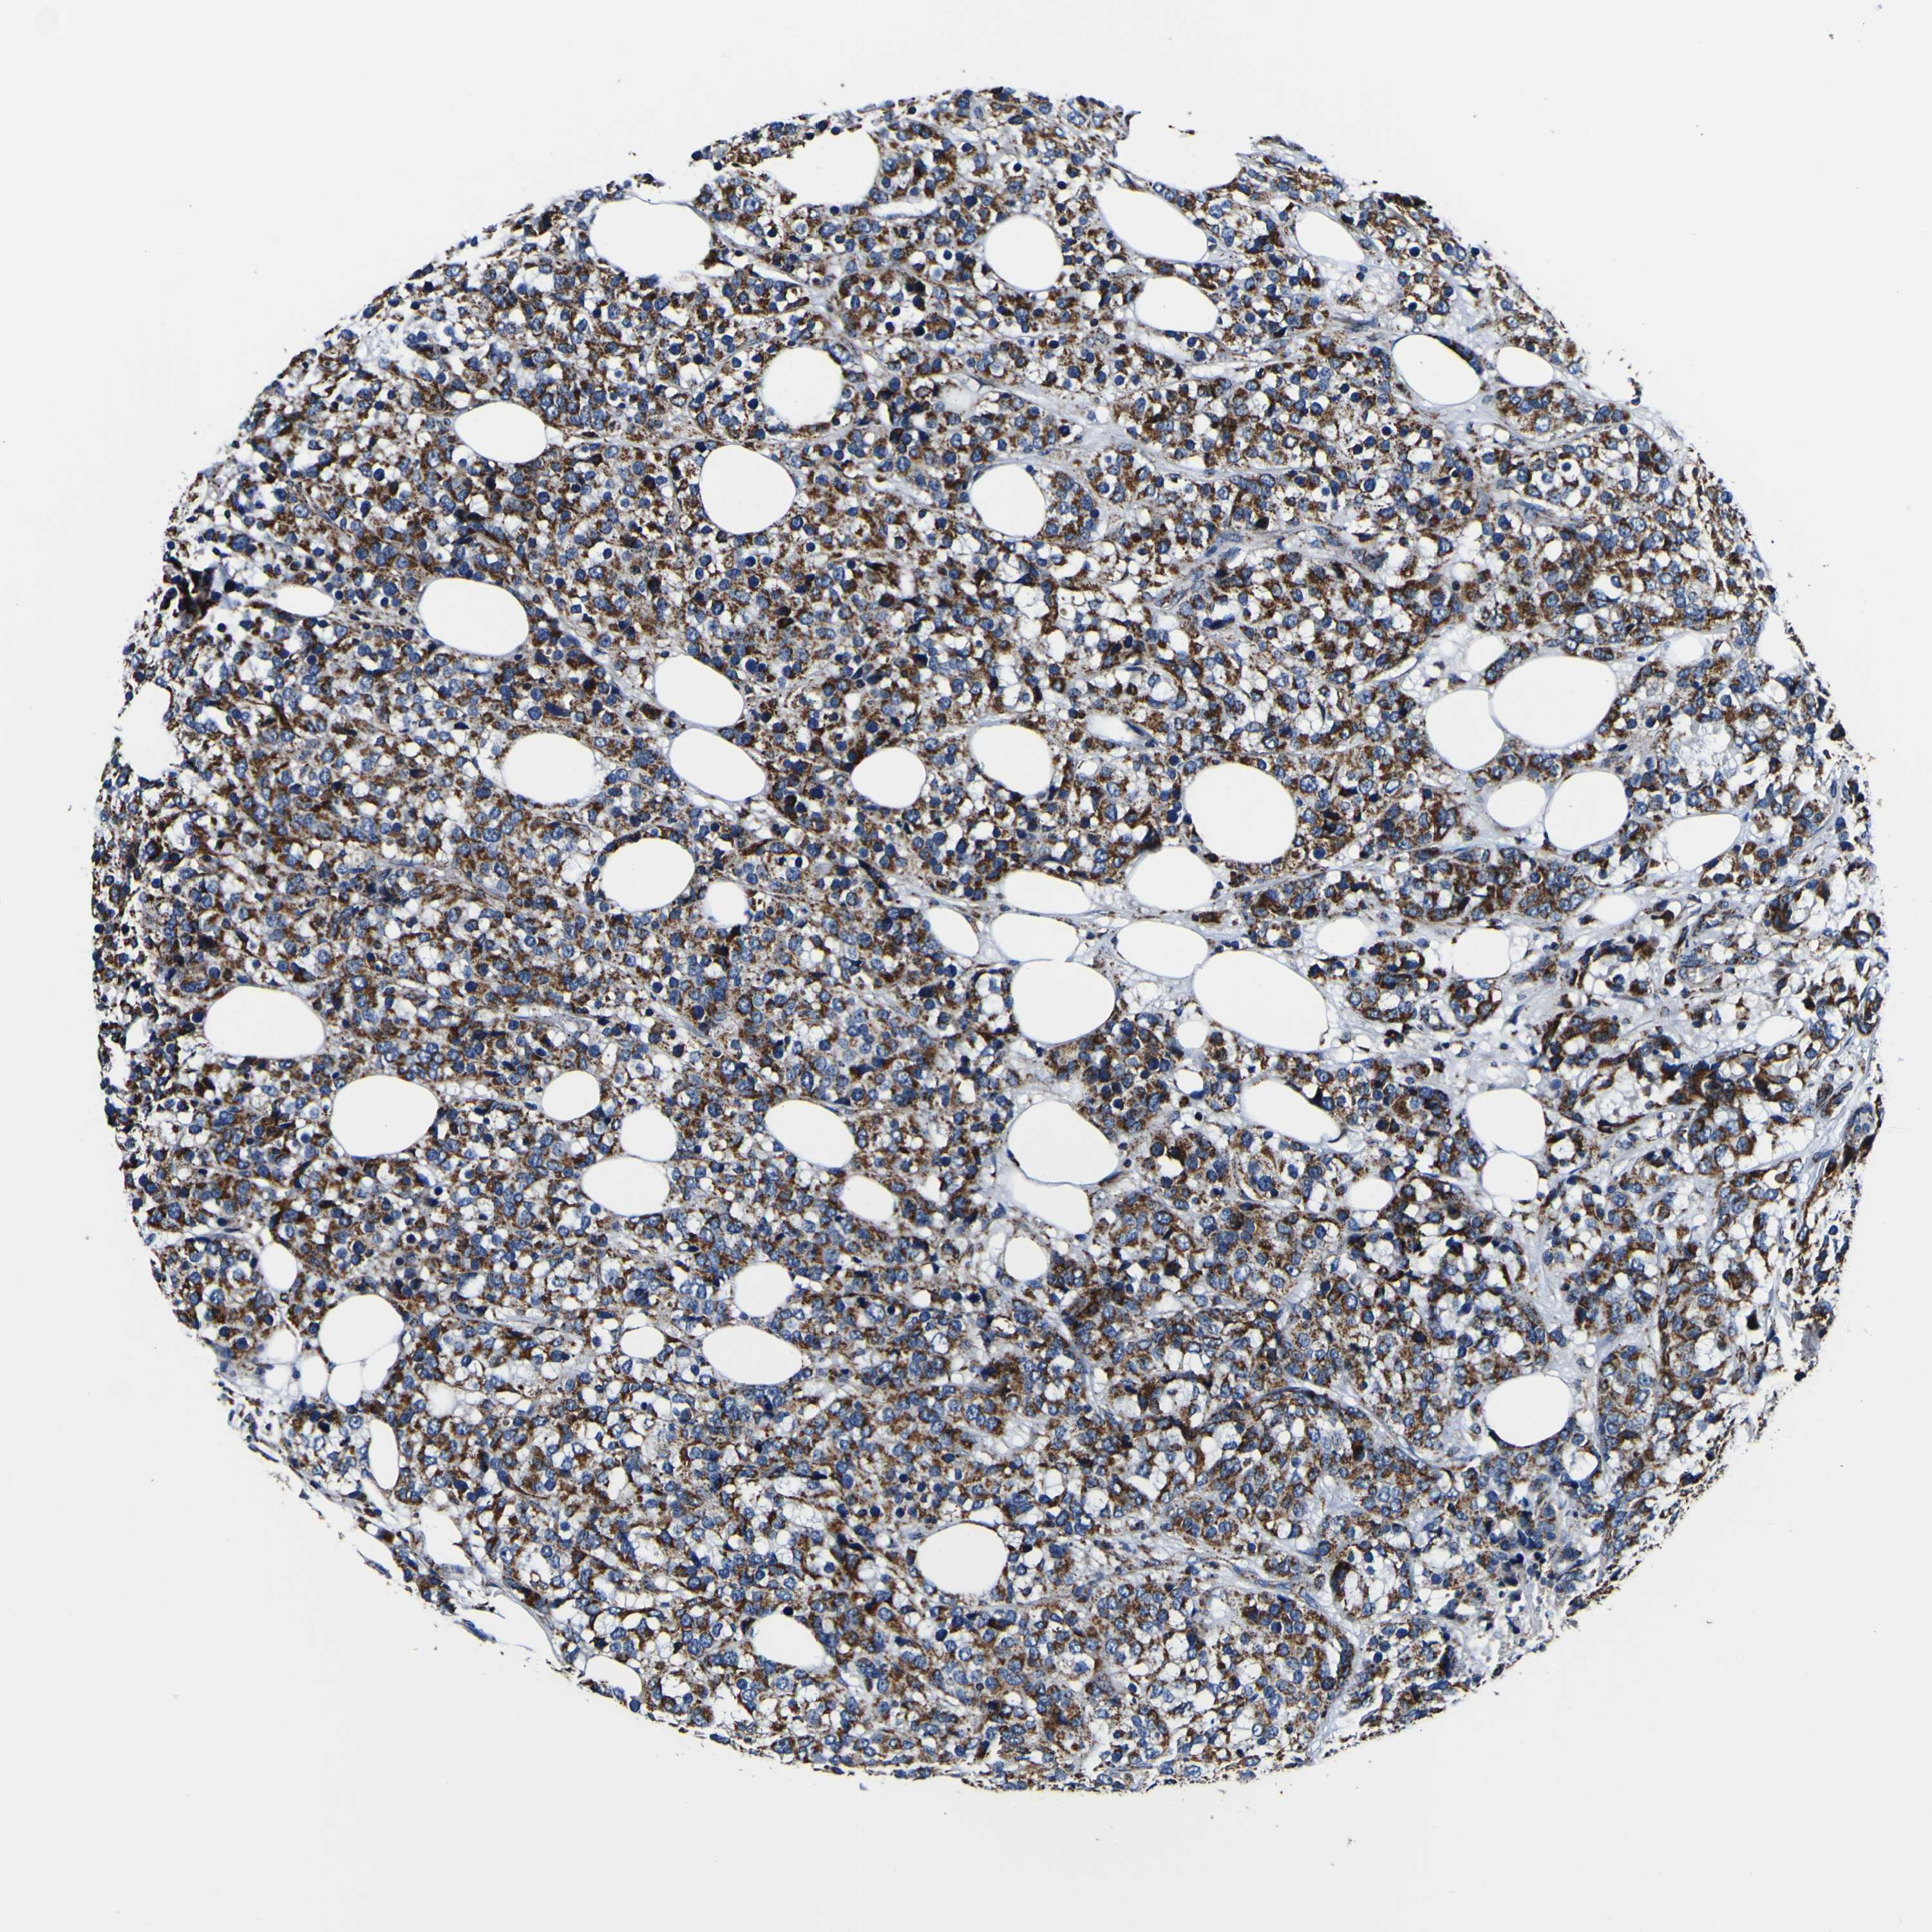

BRCA TCGA BRCA VALIDATION PROTEIN EXPRESSION